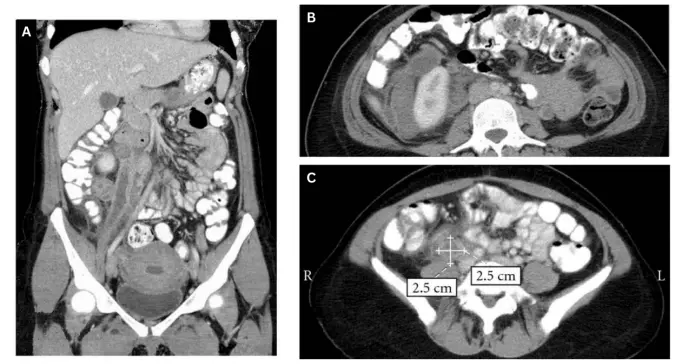

A pesar de presentar fiebre de 39.5°C y escalofríos, inicialmente fue tratada por una infección urinaria. Cuando los síntomas persistieron, una tomografía computarizada reveló una vena ovárica derecha trombosada de 8x5x5 centímetros.

El segundo caso correspondió a una joven de 19 años que tres semanas después de una cesárea para gemelos desarrolló una masa abdominal del lado derecho y dolor abdominal. Los estudios de imagen mostraron estructuras tubulares dilatadas que se extendían desde la vena renal derecha hasta el ovario, midiendo 10x6x5 centímetros.

La tomografía computarizada pélvica es el método diagnóstico de elección, con una sensibilidad del 100%, comparada con el 52% de la ecografía Doppler. Las imágenes muestran una vena agrandada con características específicas que permiten confirmar el diagnóstico.